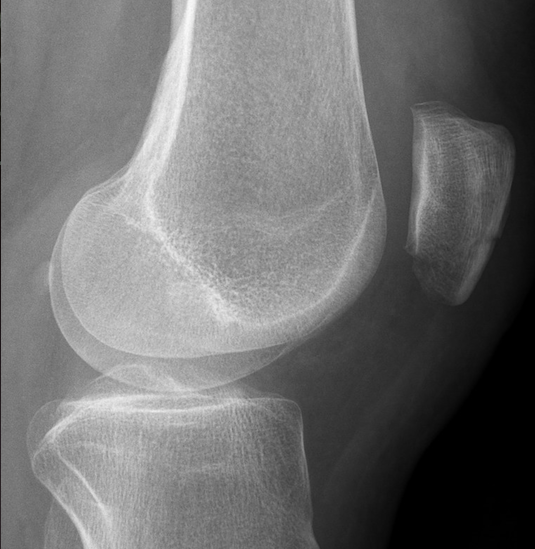

Eco musculoesquelético: Se visualiza línea hiperecogénica que atraviesa perpendicular a la cortical compatible con fractura de rótula. Tendón rotuliano ligeramente anecoico en inserción, sin datos de rotura.

Se solicita Rx para completar estudio.

Fractura de polo inferior de rótula.

Ante los hallazgos se deriva a Urgencias de Traumatología donde confirman diagnóstico.